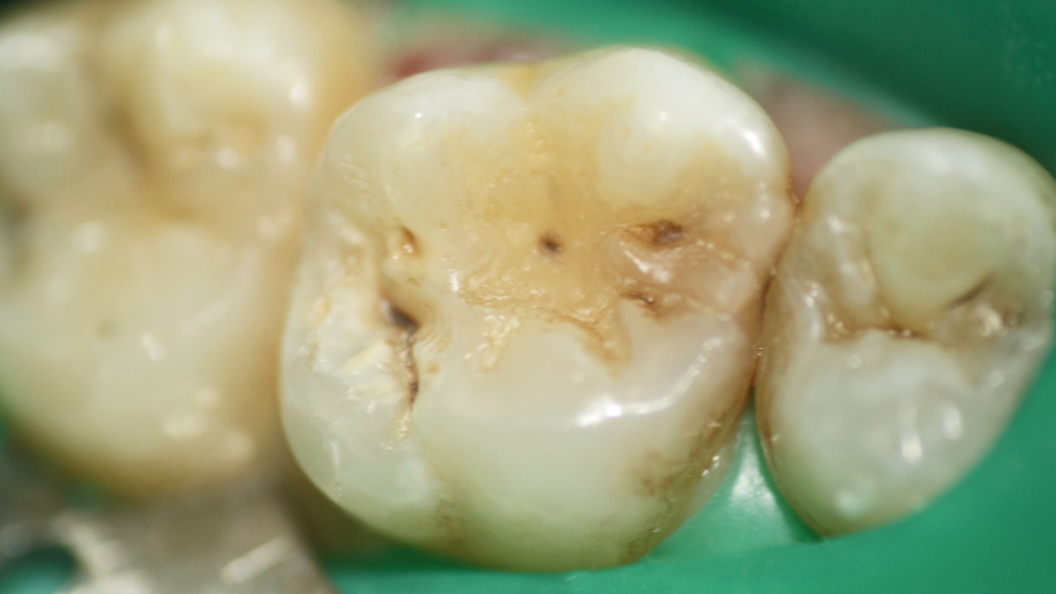

В «Стоматологию комфорта» обратился пациент с жалобами на застревание пищи между зубами на верхней челюсти справа. После осмотра врач Галухина Карина Николаевна диагностировала кариес дентина 1.6 зуба. Было принято решение о лечении кариеса при помощи композита Filtek Posterior А3. После процедуры пациенту рекомендована рациональная гигиена полости рта.

Пломбировочный материал Filtek Posterior имеет оптимальную прозрачность для естественной имитации дентина. Состав способен заполнить полость зуба толщиной до 4 мм, при этом полимеризация каждого слоя длится от 15 до 20 секунд. Благодаря эффекту хамелеона материал воспроизводит невидимый цветовой переход между собственными тканями зуба и пломбой.